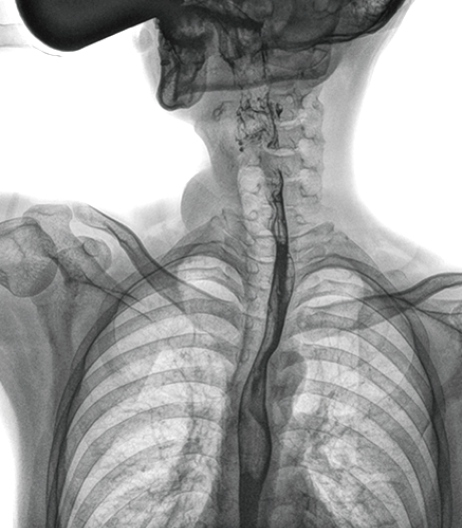

食管造影是食管病變的基本檢查方法,可以發(fā)現(xiàn)食管癌的特征性改變——食管粘膜的中斷和破壞,病人常感覺(jué)吞咽障礙,此特征在臨床中最常見(jiàn),也是早期食管癌的典型表現(xiàn)。一般伴隨的特征有管壁充盈缺損、龕影、軟組織塊影、食管腔狹窄等;在透視下還可看到食管壁僵硬、蠕動(dòng)緩慢等。

與過(guò)去的數(shù)字胃腸機(jī)比較,動(dòng)態(tài)DR圖像分辨率高,對(duì)食管的全景觀察,局部粘膜破壞、中斷,管腔狹窄以及病灶范圍的顯示清晰度明顯更優(yōu)。

上消化道造影高清圖像